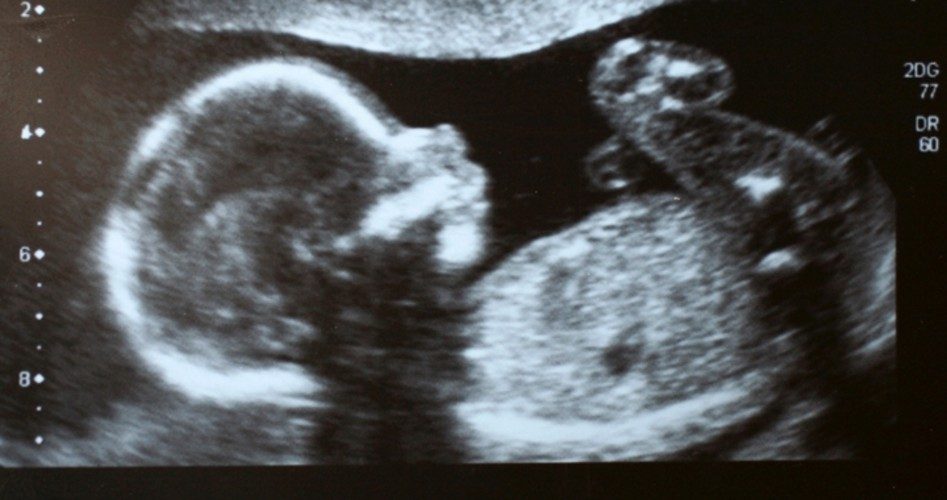

Studies have revealed that an unborn child can feel pain in the womb as early as eight weeks, though the scientific community seems to have latched on to the 20-week marker, at which time the unborn have all of the necessary body parts to experience pain, such as pain receptors, spinal cord, nerve tracts, and thalamus.